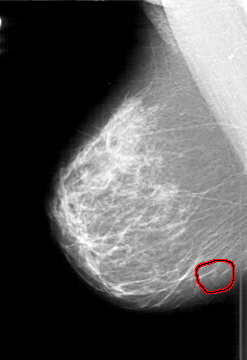

D_4197_1.RIGHT_MLO

RIGHT_MLO LINES 5746 PIXELS_PER_LINE 3946 BITS_PER_PIXEL 12 RESOLUTION 43.5 OVERLAY

FILE: D_4197_1.RIGHT_MLO.OVERLAY

TOTAL_ABNORMALITIES 1

ABNORMALITY 1

LESION_TYPE CALCIFICATION TYPE PUNCTATE DISTRIBUTION CLUSTERED

ASSESSMENT 0

SUBTLETY 2

PATHOLOGY BENIGN

TOTAL_OUTLINES 1

BOUNDARY